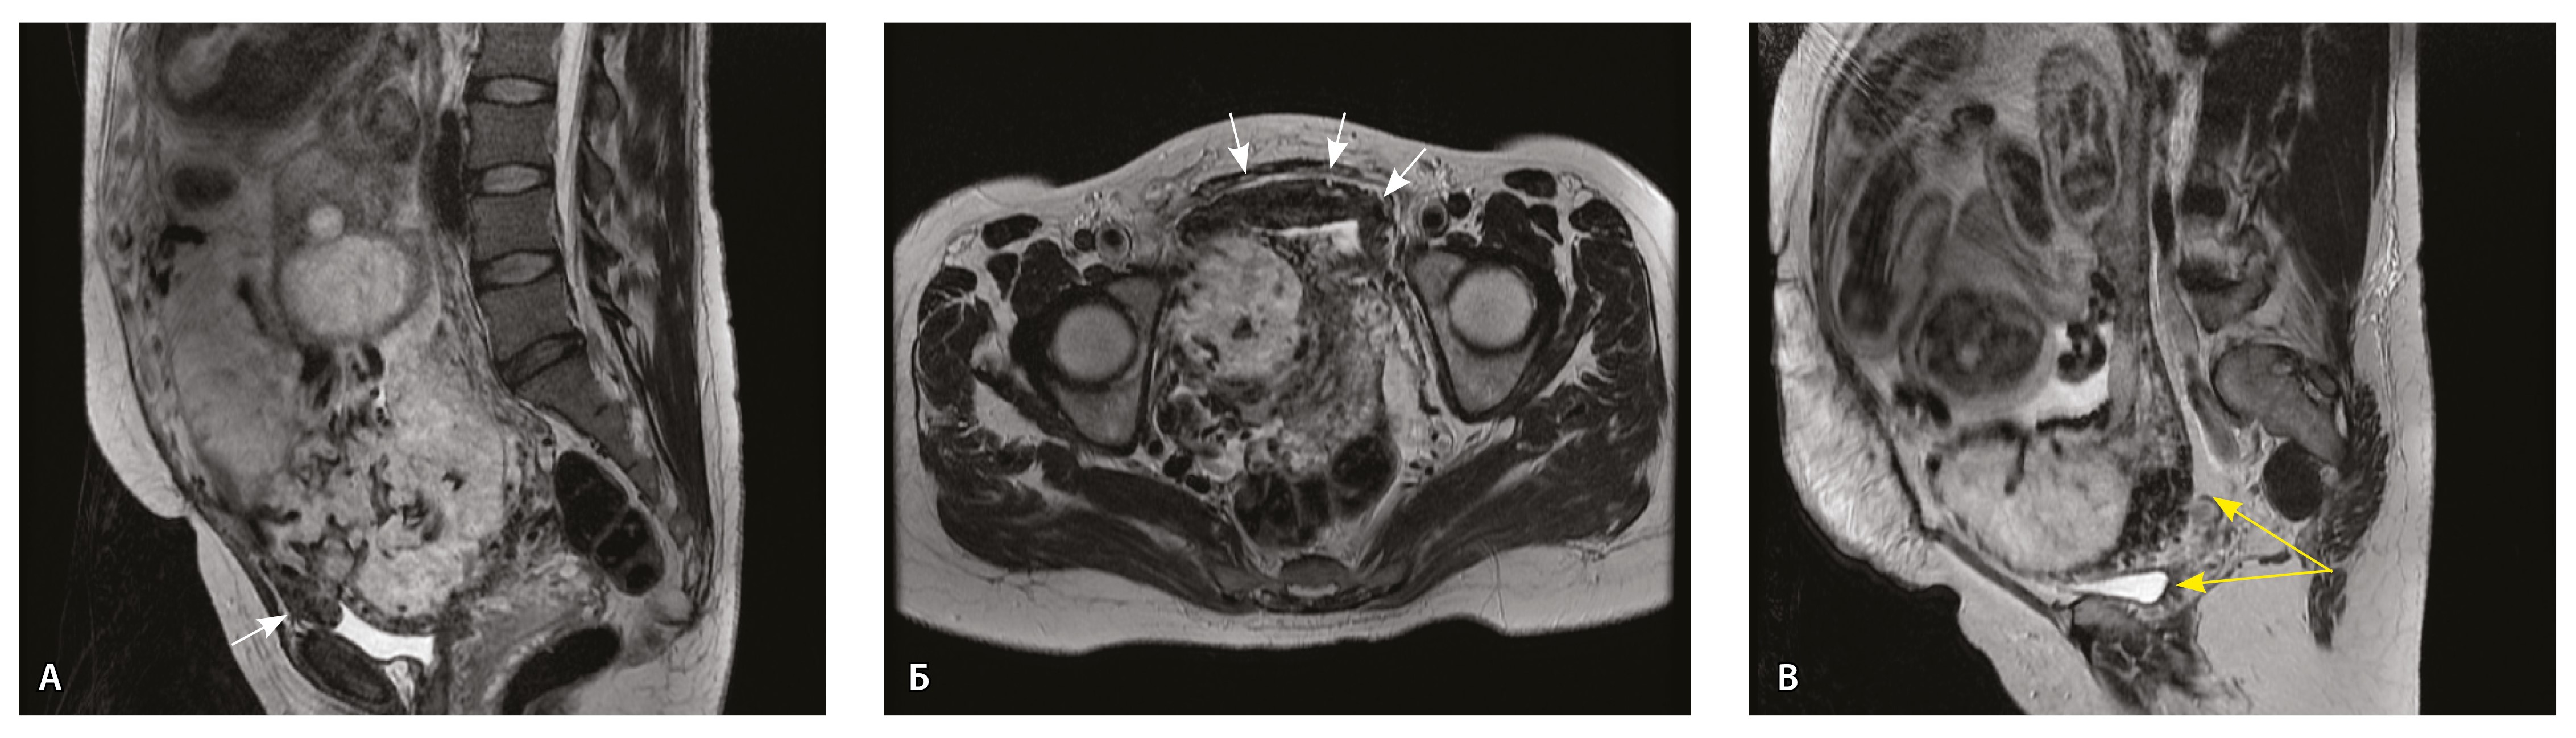

Детальному патоморфологическому исследованию с прицельным изучением маточно-плацентарной области подвергли удаленный хирургическим путем материал 30 (45,5%) пациенток: у 3 из них по данным МРТ диагностировано плотное прикрепление, у 10 – pl. accreta, у 3 – pl. increta и у 14 – pl. percreta. Мы сопоставили данные гистологического исследования и МРТ-картину. Получены следующие результаты патоморфологического исследования: отсутствие патологического прикрепления плаценты установлено у 6 (20%) пациенток, pl. accreta – у 9 (30%), pl. increta – у 13 (43,3%), pl. percreta – только у 2 (6,7%) пациенток. Pl. percreta представляла собой спайки и сращения между поверхностью матки и задней стенкой мочевого пузыря на фоне истонченного маточного сегмента. Признаков прорастания и выхода плаценты за пределы маточной стенки и в другие органы по данным гистологического исследования не отмечалось ни в одном случае.

Сосуды 5-го типа. Наличие гиперваскуляризации за пределами матки по данным МРТ, на границе с мочевым пузырем с вовлечением его стенки, сосуды в области перешейка матки, параметрия, в том числе в сочетании с признаками фиброза, наличием рубцово-спаечных изменений и др. Можно предположить, что сосуды 5-го типа являются аналогом pl. рercreta PAS 3b, 3c (рис. 15).

Рис. 15. Беременность 34 недели, pl. percreta, PAS 3b по FIGO (A, Б), PAS 3c по FIGO (В). На магнитно-резонансных томограммах в режиме Т2-взвешенного изображения в сагиттальной (A, В) и аксиальной (Б) плоскостях определяется гиперваскуляризация в области выраженно истонченного нижнего маточного сегмента с распространением сосудов на заднюю стенку мочевого пузыря в области дна (белые стрелки), в область перешейка матки (желтые стрелки)

Данный вариант в патоморфологической картине наиболее сложен для оценки ввиду того, что такие структуры, как параметрий, перешеек матки, стенка мочевого пузыря, обычно не предоставляются в виде макропрепаратов, поэтому визуальные методы, в частности МРТ, могут с большей точностью оценить вовлеченность смежных структур. На микропрепаратах данный вариант инвазии плаценты сочетается с рубцово-спаечными изменениями задней стенки мочевого пузыря с нижним маточным сегментом (рис. 16).

Рис. 16. Гистологическое исследование маточно-плацентарного сегмента при pl. percreta, определенной по данным магнитно-резонансной томографии. Окраска пикрофуксином по Маллори (красный цвет – мышечные волокна, голубой – соединительная ткань). Стенка мочевого пузыря плотно сращена с истонченным маточным сегментом, характеризуется наличием кровеносных сосудов (синяя стрелка). Фиброз задней стенки мочевого пузыря, разобщенные мышечные пучки, замурованные в соединительную ткань (поле отмечено пунктиром). Инвазия ворсин плаценты в бухты миометрия (помечена черным треугольником). Слизистая мочевого пузыря показана стрелкой. Ретроплацентарная гематома помечена звездочкой. Коллаж из 12 фото при увеличении × 100

Как видно на рис. 17, сосуды 5-го типа встречались только при глубокой инвазии плаценты по типу pl. percreta (gr 5) (р < 0,001, хи-квадрат Пирсона).

Сосуды 5-го типа определялись только у пациенток с pl. percreta (77,8%) по данным МРТ (PAS 3b, 3c по FIGO). Визуальная картина была обусловлена наличием гиперваскуляризации по поверхности матки в том числе на границе с мочевым пузырем, перешейком матки и параметрием. Нередко подобные изменения сочетались с признаками фиброза. При патоморфологическом исследовании в этой группе пациенток признаком pl. percreta считался рубцово-спаечный процесс с задней стенкой мочевого пузыря, в том числе в сочетании с сосудами 4-го типа, что было обнаружено всего у 2 пациенток. В то же время в литературе рl. percreta описана как редкое проникновение ворсин за пределы серозной оболочки матки в соседние органы (заднюю стенку мочевого пузыря, перешеек матки, параметрий), подтвержденное патоморфологически, хотя представленные случаи достаточно дискутабельны и не имеют четкого патоморфологического подтверждения [21, 22]. В нашем исследовании не удалось обнаружить ворсины хориона за пределами матки в смежных органах ни в одном из наблюдений. По нашему мнению, истонченный нижний маточный сегмент вместе с различного рода гиперваскуляризацией серозной оболочки матки не может быть единственным достоверным признаком pl. percreta, так как в составе стенки определяется атрофичный миометрий с рубцовой тканью и серозная оболочка матки оказывается неповрежденной. При этом такие структуры, как параметрий, перешеек матки, стенка мочевого пузыря, обычно не предоставляются для исследования в виде макропрепаратов, а в процессе операции удаляется лишь часть стенки матки. Ввиду этого сосуды на наружной поверхности матки лучше визуализируются при инструментальных методах исследования, а не при гистологическом исследовании. В ходе оперативного лечения сосуды могут быть повреждены, также они спадаются, меняется их кровенаполнение, поэтому картина МРТ может существенно отличаться от патоморфологической. Тем не менее проведенный нами анализ сосудов стенки матки показал четкую корреляцию между увеличением диаметра и количества сосудов как в миометрии, так и в составе серозного покрова матки с увеличением степени приращения плаценты. Ряд патоморфологов по-прежнему считает pl. percreta мифом. Но в клинической практике и в практике врачей-рентгенологов на основании МР-признаков данный вариант приращения выделяется и занимает важное место. Для наиболее точной диагностики данные патоморфологического исследования, визуальных методов диагностики, в частности МРТ, интраоперационная картина должны быть оценены не по отдельности, а в совокупности [23].